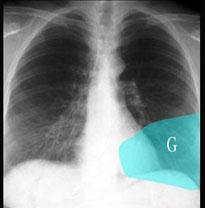

问题 在图所示正常胸部X线影像图像上,该英文字母所代表的肺段为 ( )

选项 A、后基底段 B、背段 C、前基底段 D、外基底段 E、内基底段

答案 C